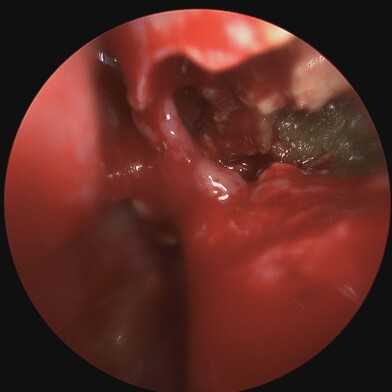

On the other hand, Chronic Sinusitis / Rhinosinusitis (CRS) is an inflammation and swelling of the sinus lining lasting longer than 12 weeks, often associated with persistent symptoms despite treatment. It can be caused by infections (bacterial / viral / fungal), allergies, environmental irritants like pollutants, anatomical abnormalities (e.g. nasal polyps) or autoimmunological factors. Patients with CRS display symptoms associated with the acute type along with headaches, a diminished sense or loss of smell (Hyposmia or Anosmia), or post-nasal drip.

Diagnosing chronic rhinosinusitis involves a comprehensive evaluation, which may include medical history and physical examination, nasal endoscopy, imaging studies, allergy testing, and conducting nasal and sinus cultures.

Treatment can be initiated with regular medications like nasal steroid sprays, anti-histamine tablet and sprays, antibiotics, nasal saline sprays, or oral corticosteroids. But specific problems causing rhinosinusitis may be treated with Functional Endoscopic Sinus Surgery (FESS).